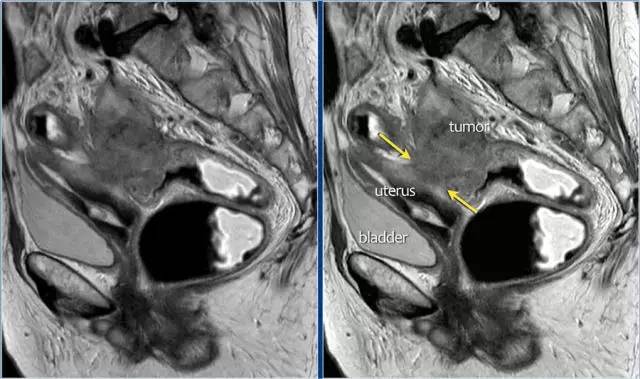

图 22 浸润到子宫后壁的肿瘤